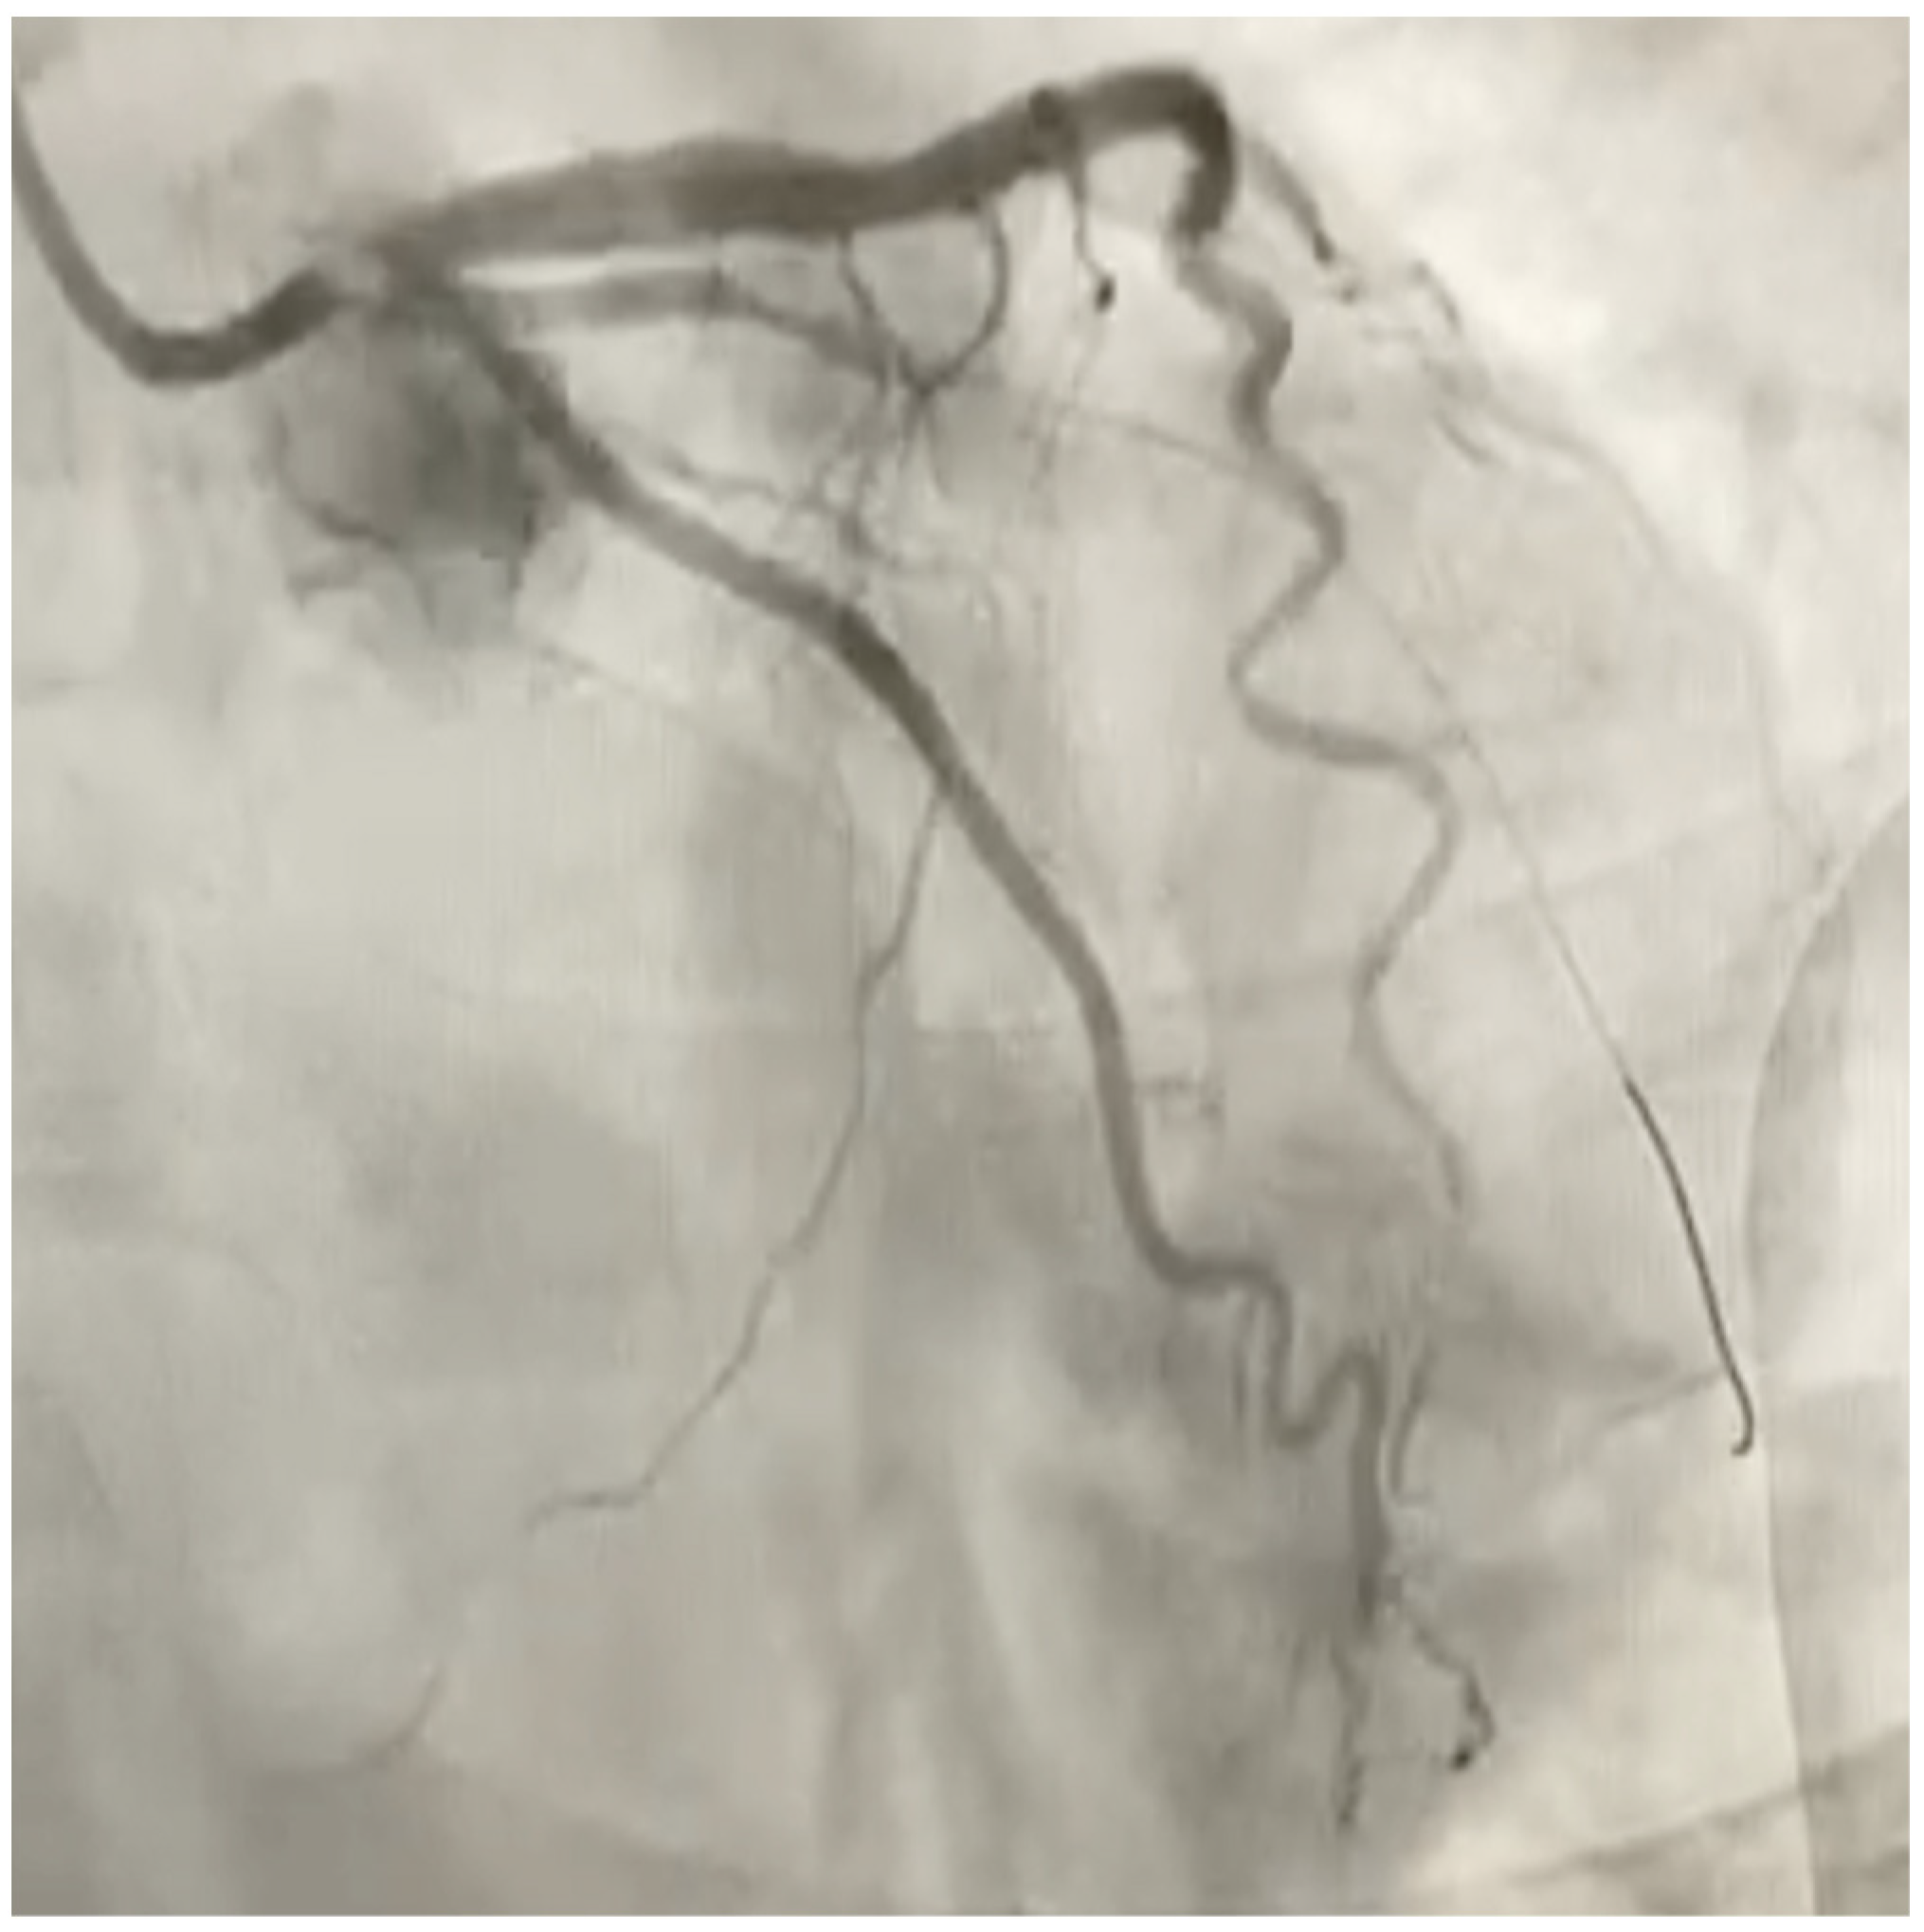

Therefore, he was sent to the emergency department of our hospital where hematochemical examinations were performed documenting increased indices of myocardiocytosis (in particular troponin I hs of 3492 ng/L). Post diagnosis of NSTEMI, the patient was taken to the hemodynamics room and underwent coronary study documenting subocclusion of the first marginal branch (figure, treated with medicated balloon (Figure 2). During hospitalization, color-doppler echocardiogram was performed documenting hypokinesis of the SIV and apex proper, preserved global systolic function (FE 55%), grade I diastolic dysfunction (E/A 0,8), mild mitral insufficiency and mild tricuspid insufficiency.

Figure 2. Coronary study documenting subocclusion of the first marginal branch.